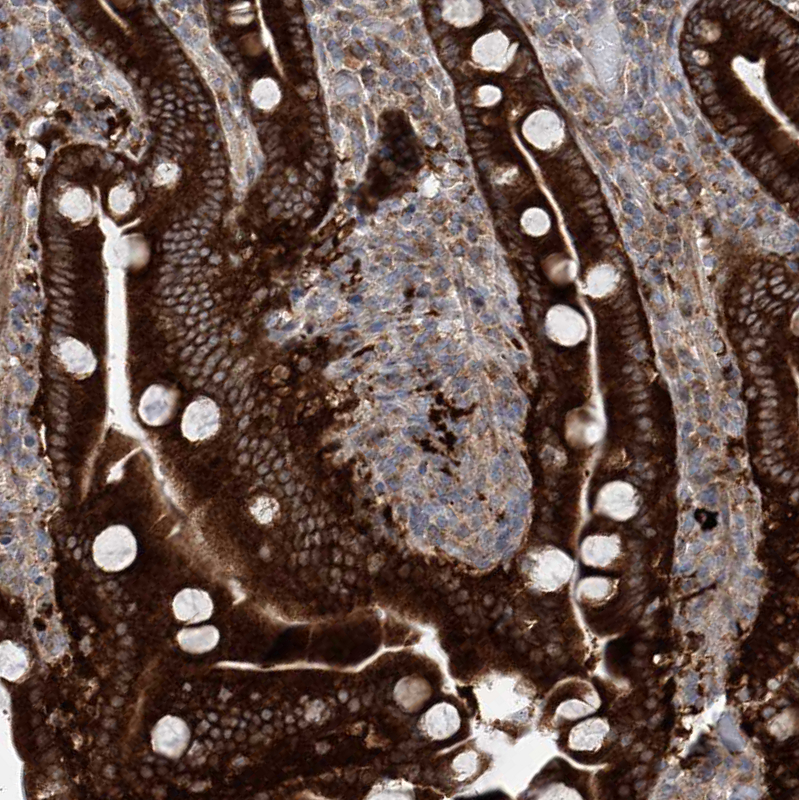

Immunohistochemistry analysis in human duodenum and tonsil tissues using HPA030169 antibody. Corresponding KLC4 RNA-seq data are presented for the same tissues.